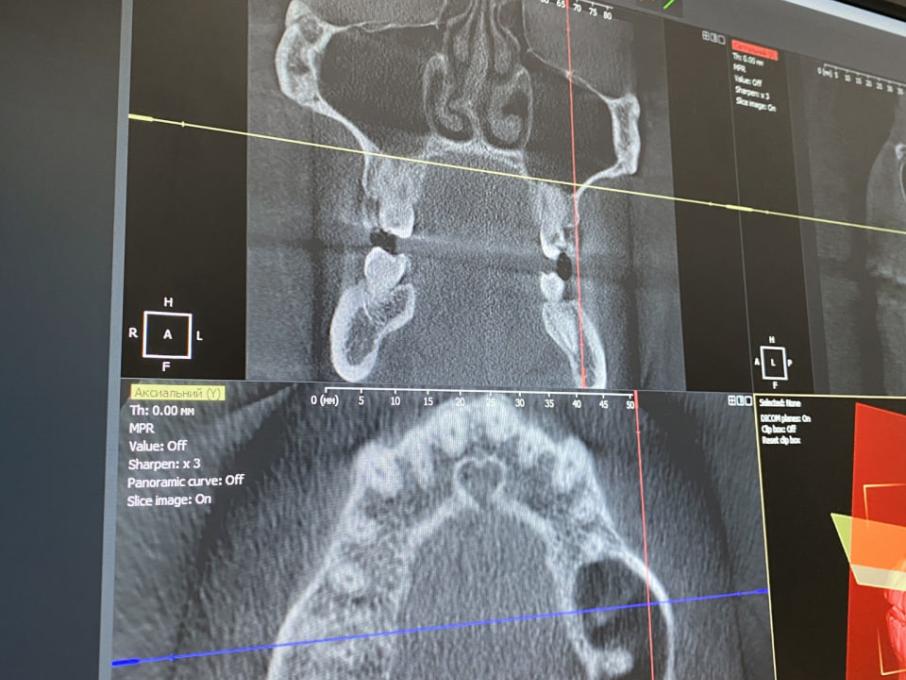

Спектр услуг клиники охватывает все направления современной стоматологии, с акцентом на сохранение естественности и функциональности. Врачи мастерски проводят терапевтическое лечение и эндодонтию под микроскопом, что гарантирует ювелирную точность в сохранении собственных зубов пациента. Особое направление — эстетическая трансформация: создание безупречных керамических виниров и художественных реставраций, которые выглядят настолько натурально, что их невозможно отличить от настоящей эмали. Для полного восстановления улыбки в Dental Story предлагают надёжную имплантацию и протезирование с использованием современных цифровых протоколов.